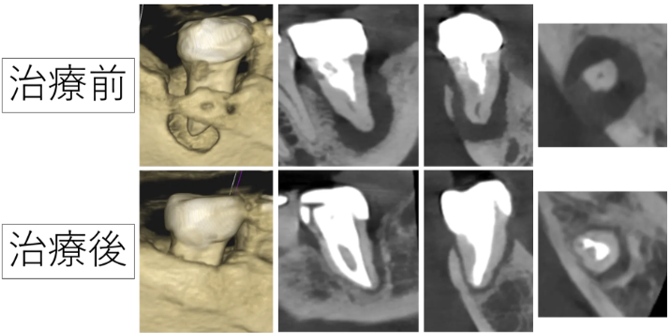

顎の骨が溶けて抜いてインプラントを勧められた歯。骨が回復するまでの記録

根の病気で顎の骨が大きく溶け、残せないと言われた歯を根の治療で治しました

根の大きな病気で骨が溶け穴に。精密な根管治療で骨が再生した症例